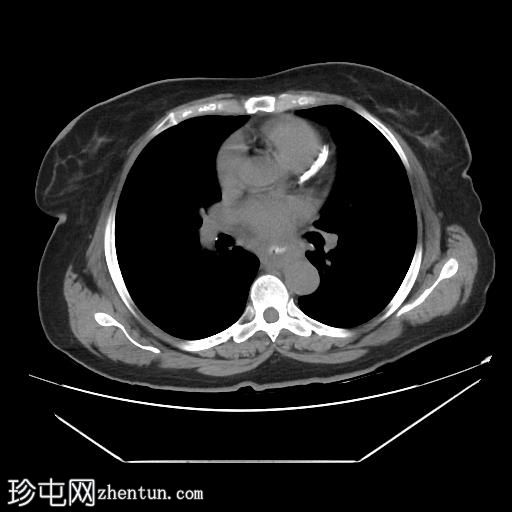

轴位增强扫描

动脉期

中段食管壁增厚,提示

肿瘤

浸润,长约10厘米。肿块与左主支气管后壁及降主动脉紧密接触。未见侵犯邻近结构的迹象,也未触及区域淋巴结肿大。